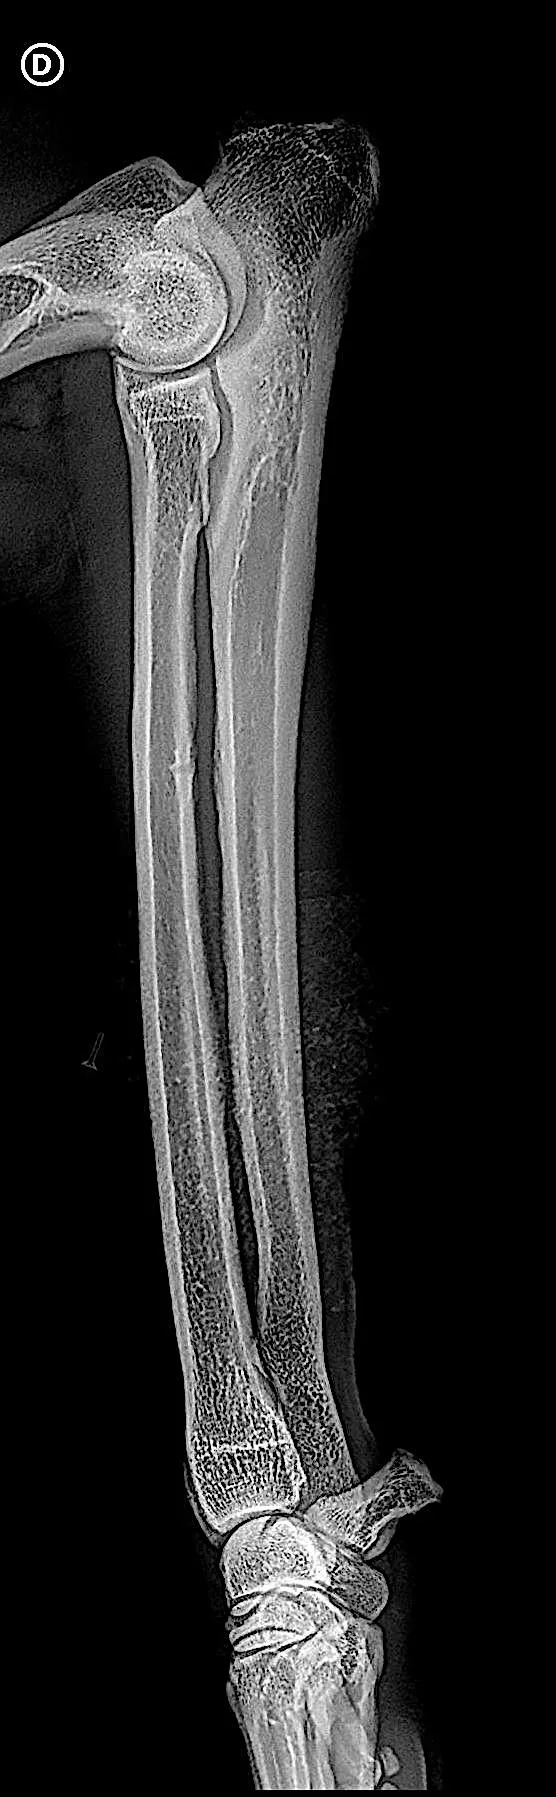

Cliché officiel d'un dépistage de dysplasie du coude

La dysplasie du coude correspond à un développement pathologique de l’articulation du coude, liée à des altérations morphologiques de l’humérus, du radius ou de l’ulna. Les symptômes cliniques peuvent être des boiteries précoces, une altération de la mobilité articulaire et notamment de sa flexion et une pathologie dégénérative arthrosique précoce.

Pour confirmer le diagnostic, des radiographies des articulations concernées (hanche et/ou coude) sont nécessaires. Cet examen se réalise généralement sous sédation ou anesthésie légère, afin de garantir une position précise et sans douleur pour l’animal. Une contention optimale est indispensable pour obtenir des clichés exploitables, notamment pour les dépistages officiels demandés chez les chiens de race.

Les radiographies officielles réalisées sont alors envoyées à un lecteur agréé par la centrale canine, qui attribuera un score de dysplasie selon une classification standardisée.